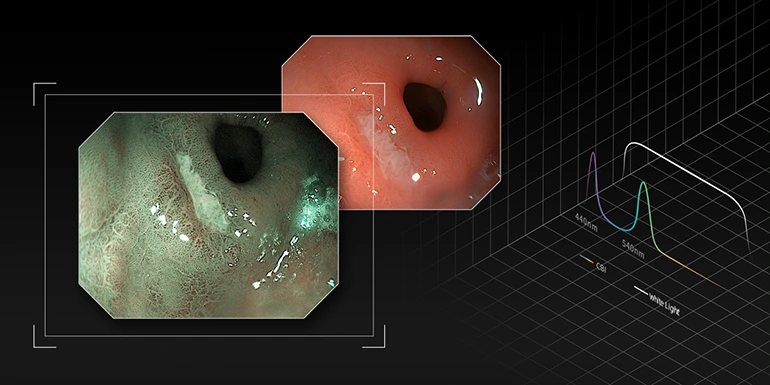

Режим CBI

Оптическая хромоэндоскопия (CBI) демонстрирует более высокий контраст между слизистой оболочкой и кровеносными сосудами, что помогает дифференцировать ряд поражений слизистой оболочки и подчеркнуть распределение подслизистых сосудов.